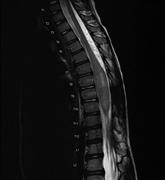

The use of dual growing rods to correct spinal deformity secondary to a low-grade spinal cord astrocytoma

Elizabeth N. Kuhn and others

Journal of Surgical Case Reports, Volume 2015, Issue 10, October 2015, rjv128, https://doi.org/10.1093/jscr/rjv128